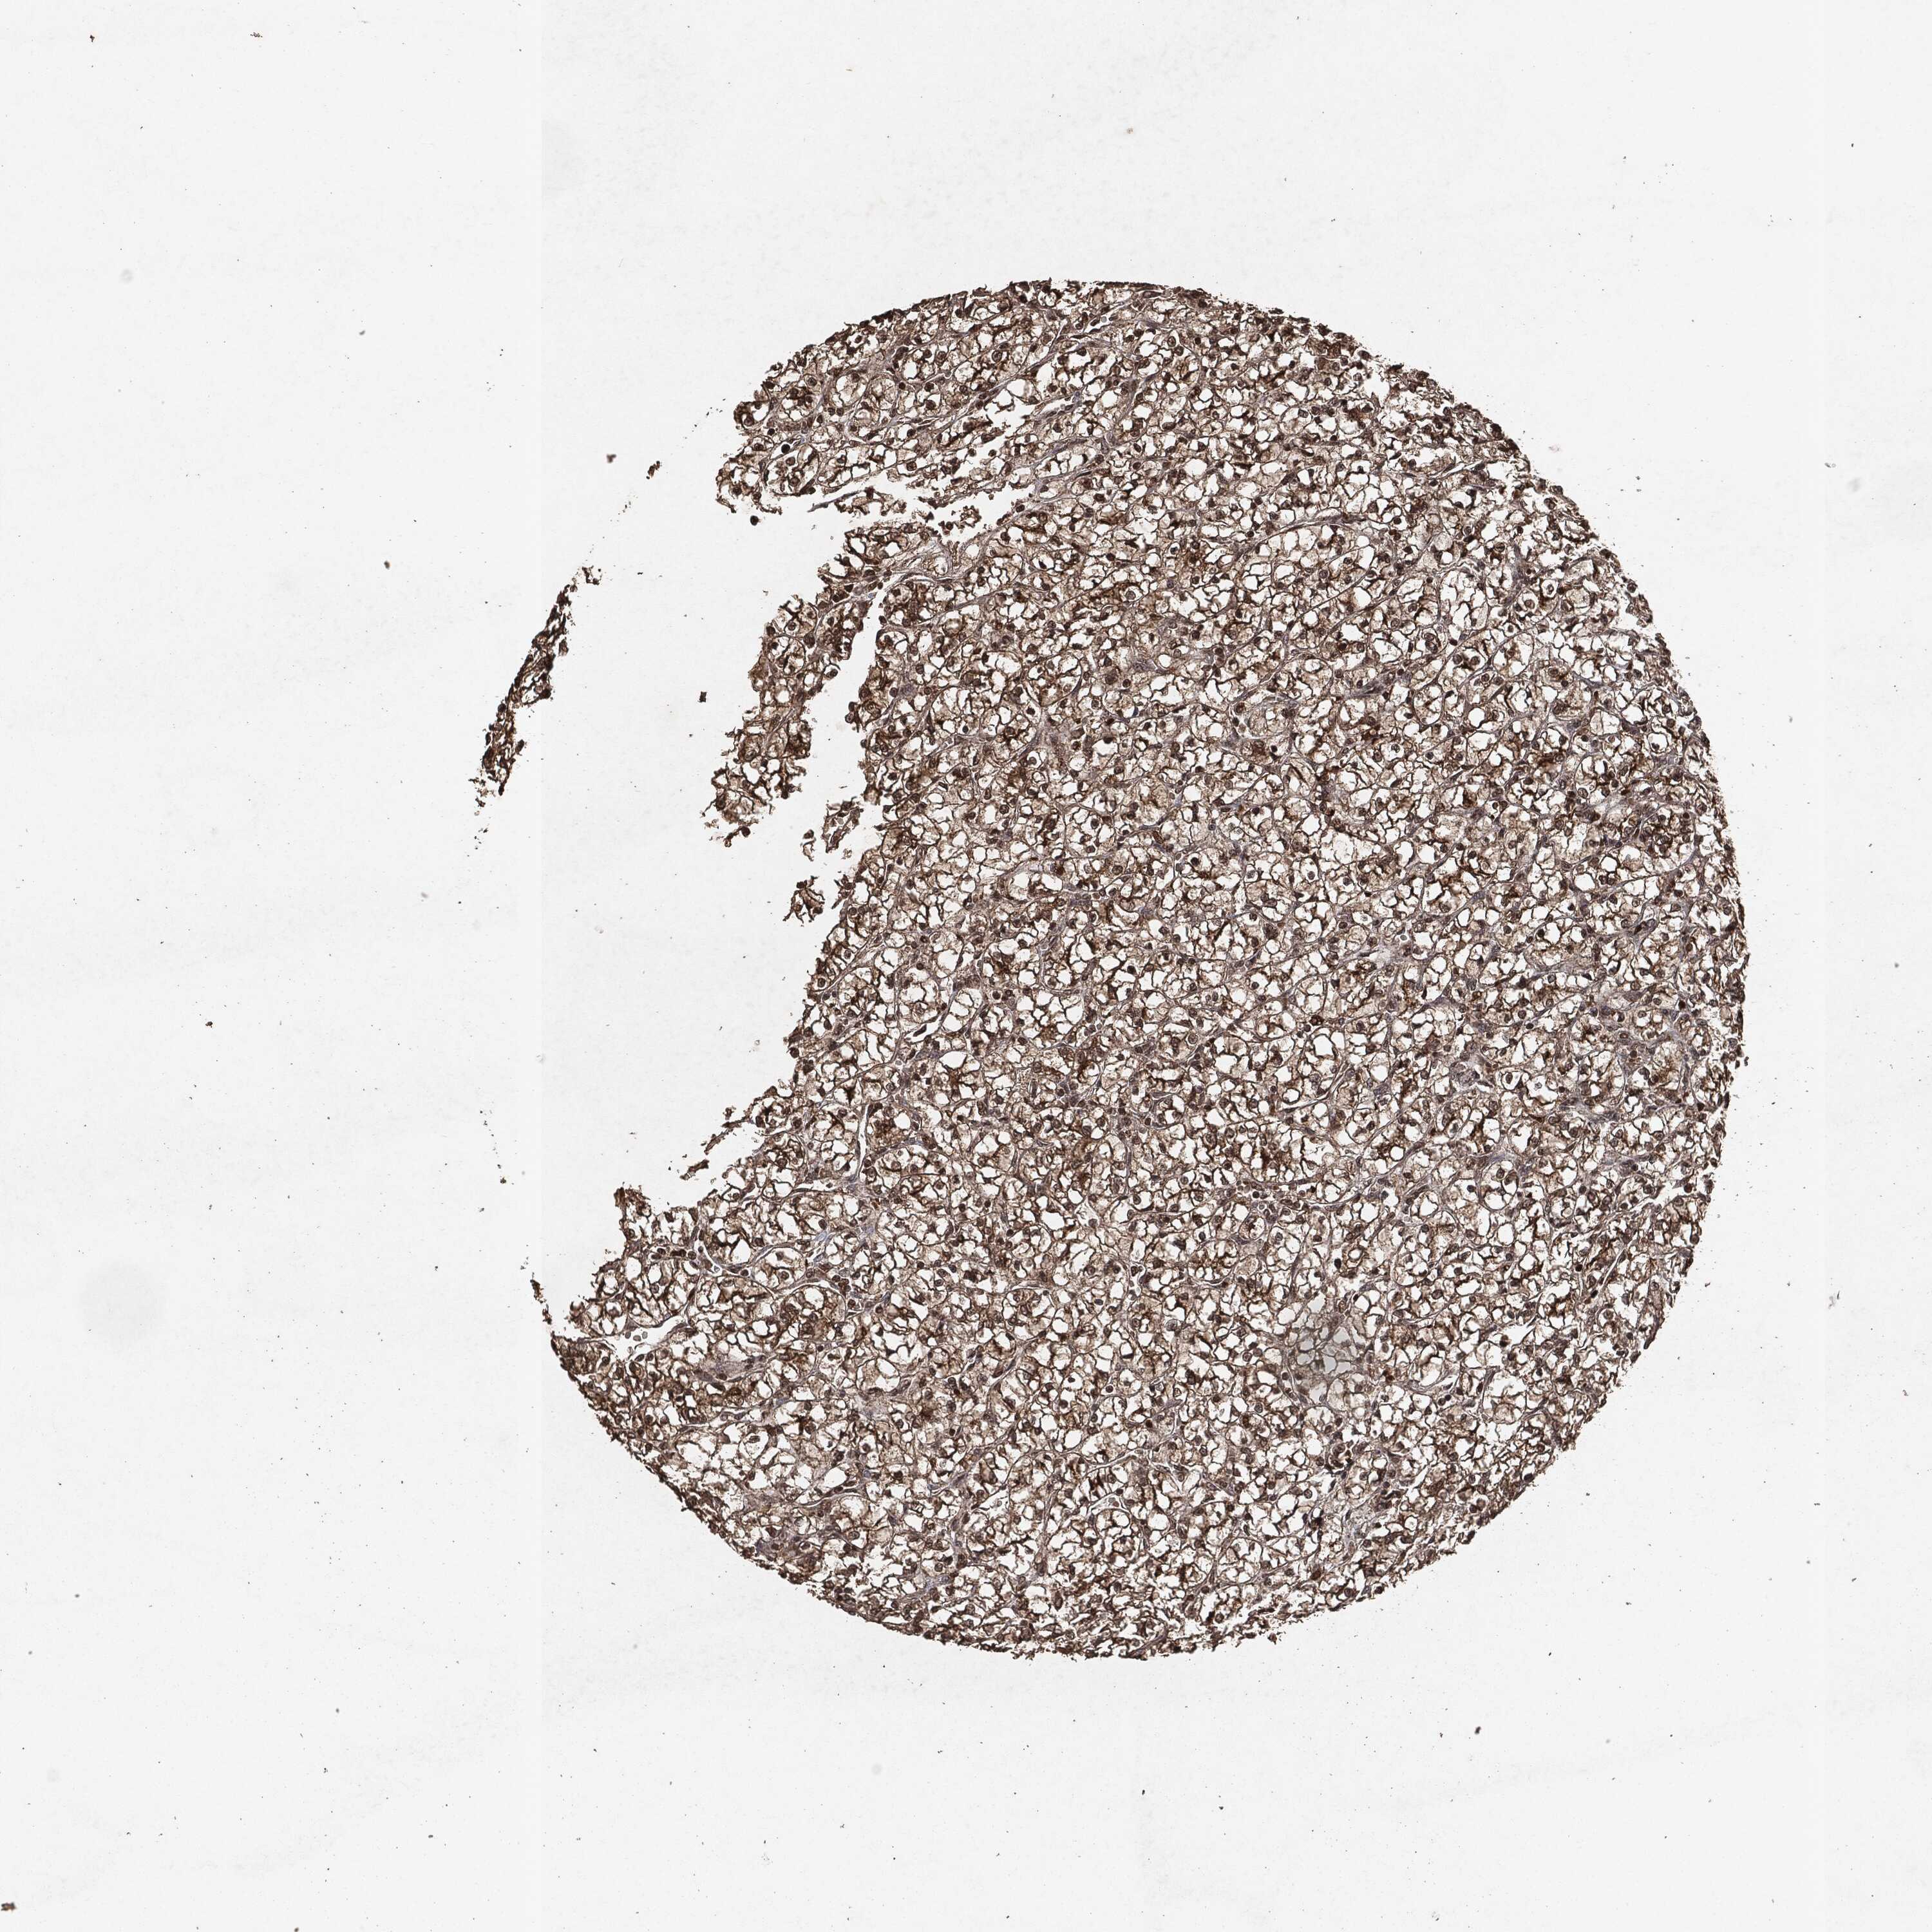

KIDNEY RENAL PAPILLARY CELL CARCINOMA (TCGA) - Interactive survival scatter ploti

EGFR is not prognostic in Kidney Renal Papillary Cell Carcinoma (TCGA)